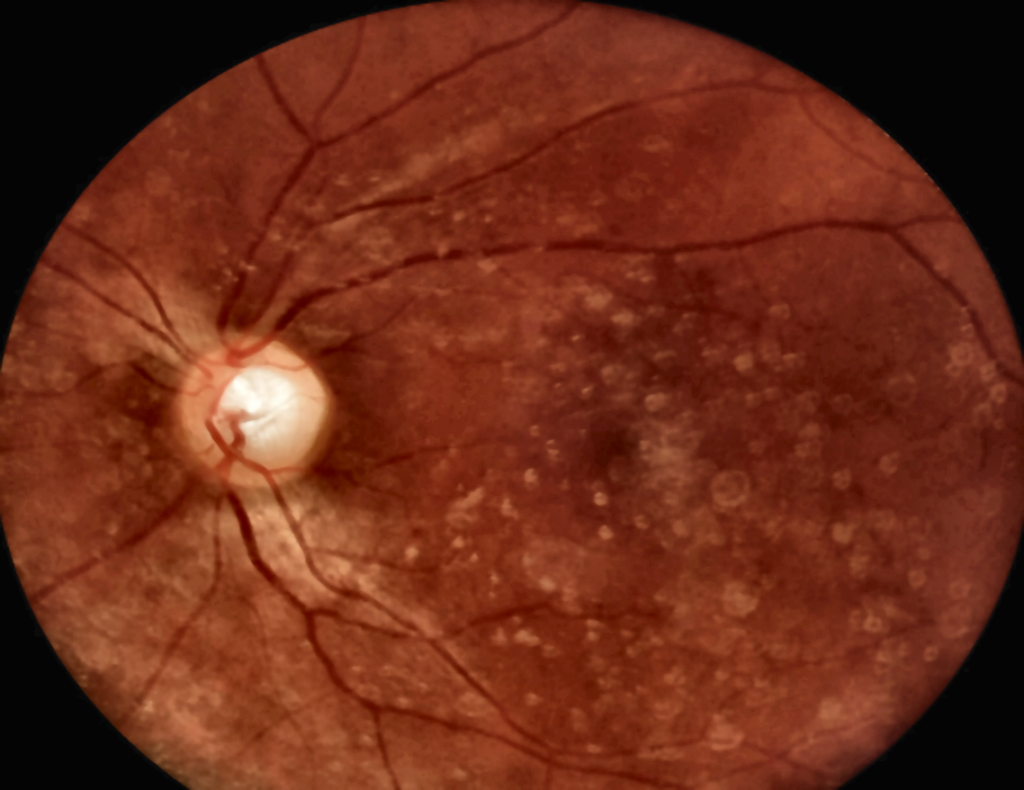

- acompanhamento de suspeitas ou alterações relacionadas à degeneração macular

- rastreio e monitoramento de retinopatia diabética

- controle de lesões, hemorragias ou alterações vasculares que podem mudar com o tempo

Quando falamos em prevenção de perda visual no diabetes, o objetivo é detectar alterações cedo. A retinografia aparece com frequência porque padroniza imagens e viabiliza comparações ao longo do tempo — inclusive em modelos de rastreamento, triagem e encaminhamento para especialistas quando necessário.

Isso não significa que “todo diabético precisa fazer o exame toda hora”. Significa que, junto com outros métodos, a fotografia do fundo do olho pode ajudar a identificar quem precisa de acompanhamento mais próximo, tratamentos específicos e revisões em intervalos menores.